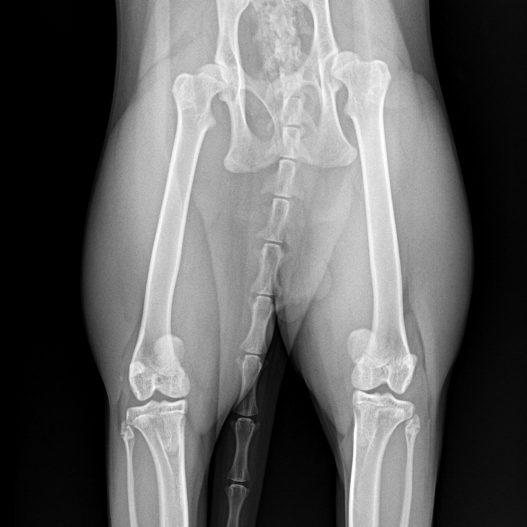

보다 정확한 원인 평가를 위해 본원에서는

방사선(X-ray) 검사를 통한 정밀 진단을 진행했습니다.

정밀 진단 진행 결과

루미(가명)는 양측 슬개골 내측 탈구뿐만 아니라

양측 고관절 아탈구도 함께 확인되었습니다.

이는 무릎 관절과 고관절에서 동시에 통증을 유발할 수 있는 상태로,

슬개골 탈구만 교정할 경우

보행 이상이 완전히 해소되지 않을 가능성이 높은 상황이었습니다.

루미는 양측 고관절과 슬개골이 다 문제가 되는 상태여서 수술을 한꺼번에 진행할 수 없었고,

촉진상 고양이 슬개골탈구 단계가 조금 더 높았던 좌측을 먼저 수술한 뒤

2-3개월 회복과정을 거친 후 우측 다리를 수술하기로 계획하였습니다.

좌측 슬개골 탈구 교정술과 대퇴골두절단술을 같이 진행하였습니다.